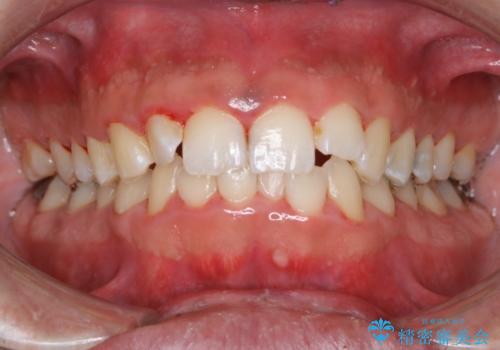

結婚式前にクリーニング希望の方

担当医 歯科衛生士